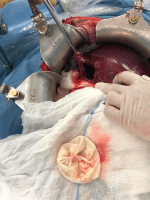

Οι εικόνες είναι από προσωπικά χειρουργεία και οι ασθενείς έχουν χορηγήσει τη συγκατάθεση τους.

Ποια θεραπεία ακολουθείται; Η θεραπεία της νόσου είναι τις περισσότερες φορές η χειρουργική επέμβαση. Κατά τη διάρκεια της, ο Γενικός Χειρουργός χρησιμοποιεί ειδικά διαλύματα για να εξουδετερώσει τα παράσιτα και έπειτα αφαιρεί όλη την κύστη. Αν χρειαστεί, ο ιατρός μπορεί να προχωρήσει σε ηπατεκτομή, αλλά αυτή η περίπτωση είναι αρκετά σπάνια. Η φαρμακευτική αγωγή μπορεί να λαμβάνεται από τον ασθενή πριν και μετά την επέμβαση. Σε περιπτώσεις που οι κύστεις έχουν μικρό μέγεθος και έχουν νεκρωθεί το χειρουργείο μπορεί να αποφευχθεί.

Ανάλογα με το κάθε περιστατικό, η επέμβαση μπορεί να διαρκέσει 2 με 4 ώρες και πραγματοποιείται είτε ανοιχτά είτε λαπαροσκοπικά.

Η επέμβαση έχει μεγάλη διάρκεια και απαιτεί έμπειρο Γενικό Χειρουργό, ο οποίος θα έχει την ικανότητα να διαχειριστεί με το σωστό τρόπο την αφαίρεση των εχινόκοκκων κύστεων καθώς η παραμονή υπολείμματος μπορεί να επιφέρει υποτροπή της νόσου. Ο Δρ. Γιακουστίδης Δημήτρης, Αναπληρωτής Καθηγητής Χειρουργικής και Μεταμοσχεύσεων, διατελεί Γενικός Χειρουργός στην Α’ Χειρουργική Κλινική του ΑΠΘ στο νοσοκομείο Παπαγεωργίου και έχει πολυετή εμπειρία στις επεμβάσεις ήπατος.